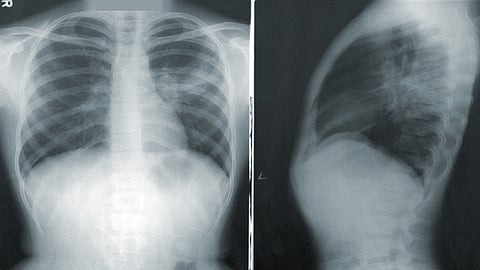

मुंबई - कोरोना संसर्गाचा वाढता प्रादुर्भाव पाहता जगभरातून कोरोनावर कसं नियंत्रण मिळवता येईल याबद्दल अनेक संशोधनं केली जातायत. यामध्ये कोरोनावर लस तर शोधली जातेच आहे. सोबतच कोरोनाची लक्षणं काय, कोरोना संक्रमण असेल तर ते किती आहे, त्याला लवकरात लावलात कसं शोधून काढता येईल यावर देखील अभ्यास सुरु आहे. याच पार्श्वभूमीवर IIT गांधीनगरमधील संशोधकांनी एक उपकरण बनवलंय. या उपकरणाद्वारा एखाद्या व्यक्तीला कोरोनाचं किती संक्रमण झालंय हे समजू शकणार आहे. एक्स रे प्रणालीवरील या उपकरणात आर्टिफिशियल इंटेलिजन्सवरचा आधार घेण्यात आलाय.

एखाद्या कोरोना संशयित रुग्णाच्या वैद्यकीय चिकित्सेआधी किंवा सोप्या भाषेत सांगायचं तर कोविड टेस्ट आधी हे उपकरण वापरलं जाऊ शकतं. इंडियन इन्स्टिट्यूट ऑफ पब्लिक हेल्थ IIPH द्वारा या आर्टिफिशियल इंटेलिजन्सवर आधारित उपकरणाचं परीक्षण आणि चाचणी केली जातेय.

कुशापाल सिंह यादव यांच्या माहितीप्रमाणे ते ज्या मॉडेलवर काम करत आहेत त्यात टेक्निकल नेटवर्कचे १२ लेयर्स आहेत. हे लेयर्स माणसाच्या मेंदूतील न्यूरॉन सारखे काम करतात. या प्रोसेसमध्ये एक्स रे फोटोजच्या माध्यमातून कोरोना संसर्गाची माहिती मिळू शकते. अमेरिकेतील प्रिन्स्टन युनिव्हर्सिटीमध्ये देखील काही संशोधक आर्टिफिशियल इंटेलिजन्सवर आधारित उपकरण बनावट असल्याची माहिती आहे.